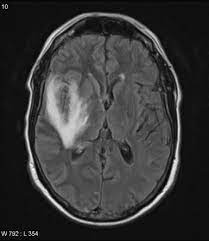

Two subtypes are recognized which differ in demographics, virus, and pattern of involvement. Become a gold supporter and see no ads. Bilateral temporal lobe t2 hyperintensity refers to hyperintense signal involving the temporal lobes on t2 weighted and flair imaging. Hypertrophic pachymeningitis is a condition where there is localized inflammatory thickening of the dura. Limbic encephalitis, mca ischaemia, tumours, effects of seizures) hyperintense t2 signal in the medial temporal lobes, inferior frontal lobes and insula basal ganglia are usually spared Reference osborn a, et al. Given the history of fever and seizures coupled with the mri findings of bilateral mesial temporal lobe changes, herpes encephalitis requires clinical consideration. The changes spare the basal ganglia, a feature which is helpful in distinguishing an mca infarct with hemorrhagic transformation from herpes simplex encephalitis, the diagnosis in this case. Mri demonstrates extensive edema in the right temporal lobe with areas of intrinsic high t1 signal, in keeping with hemorrhage. It is estimated to occur in ~2% of pati. The differential diagnoses include limbic encephalitis (paraneoplastic), gliomatosis cerebri, and status epilepticus. It is reasonable to obtain an mri when patients are asymptomatic to ensure that no other abnormality is present which may be causing a recurrent chemical meningitis (e.g. Axial t2 prominent swelling, increase t2 signal involving the left temporal lobe and insular cortex.

Mri demonstrates extensive edema in the right temporal lobe with areas of intrinsic high t1 signal, in keeping with hemorrhage. Become a gold supporter and see no ads. For a general discussion, and for links to other system specific manifestations, please refer to the article on coccidioidomycosis. This patient went on to have hsv encephalitis proven on csf pcr. This patient went on to have hsv encephalitis proven on csf pcr. Spinal hydatid disease is an uncommon manifestation of hydatid disease, caused by the larval stage of echinococcus granulosus, or less commonly e. Given the history of fever and seizures coupled with the mri findings of bilateral mesial temporal lobe changes, herpes encephalitis requires clinical consideration. Multilocularis, and describes a spectrum of disease involving the spinal cord, the spine, or both. Herpes simplex encephalitis radiology case radiopaedia mri demonstrates extensive edema in the right temporal lobe with areas of intrinsic high t1 signal, in keeping with hemorrhage. Hsv encephalitis | radiology case | radiopaedia.org. Two subtypes are recognised which differ in demographics, virus, and pattern of involvement. It is estimated to occur in ~2% of pati. Reference osborn a, et al.

Herpes simplex (hsv) encephalitis is the most common cause of fatal sporadic fulminant necrotising viral encephalitis and has characteristic imaging findings. The differential diagnoses include limbic encephalitis (paraneoplastic), gliomatosis cerebri, and status epilepticus. The basal ganglia are usually spared. Note the high signal in the caudate heads and putamen on flair. Bilateral temporal lobe t2 hyperintensity refers to hyperintense signal involving the temporal lobes on t2 weighted and flair imaging. It is reasonable to obtain an mri when patients are asymptomatic to ensure that no other abnormality is present which may be causing a recurrent chemical meningitis (e.g. For a general discussion, and for links to other system specific manifestations, please refer to the article on hydatid disease. Radiopaedia is free thanks to our supporters and advertisers.

Axial t2 prominent swelling, increase t2 signal involving the left temporal lobe and insular cortex. It is estimated to occur in ~2% of pati. Become a gold supporter and see no ads. This patient went on to have hsv encephalitis proven on csf pcr. A brain biopsy was performed and the histology was consistent with encephalitis. The differential diagnoses include limbic encephalitis (paraneoplastic), gliomatosis cerebri, and status epilepticus. Multilocularis.the larval stage is the cause of hydatid disease in humans 1. It is usually bilateral but asymmetrical. Spinal hydatid disease is an uncommon manifestation of hydatid disease, caused by the larval stage of echinococcus granulosus, or less commonly e. Limbic encephalitis, mca ischaemia, tumours, effects of seizures) hyperintense t2 signal in the medial temporal lobes, inferior frontal lobes and insula basal ganglia are usually spared It is reasonable to obtain an mri when patients are asymptomatic to ensure that no other abnormality is present which may be causing a recurrent chemical meningitis (e.g. 10 public playlist includes this case Pcr was repeated on the biopsy specimen and was positive for hsv.